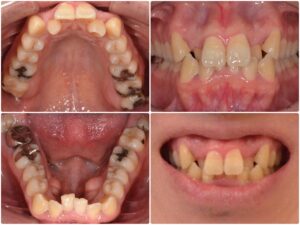

前歯部の歯並びが気になる 60代女性 2026.2.6

主訴・術前 前歯部の歯並びが気になる 術後の患者様の感想 マウスピース矯正やセラミック矯正を行って自分の納得のいく歯並びになることができたので良かったです。 マウスピースに関しては、続けられるか不安でしたが続けることができ、…